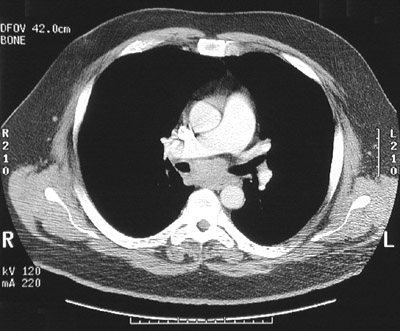

![]() | In the chest CT scan views in "bone window" above and below in the subcarinal region between the right main bronchus and the left main bronchus is a mass composed of enlarged lymph nodes. Biopsy of the mass revealed involvment by the nodular sclerosis type of Hodgkin's disease. Hodgkin's disease may involve a single group of nodes, more than one group of nodes, or may involve extranodal sites such as liver, spleen, or bone marrow. |